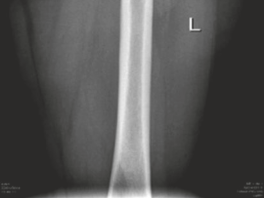

| Femoral Neck Fracture | < 1% | Prevention: Careful dislocation technique, avoiding excessive force, adequate neck osteochondroplasty. Management: Immediate reduction and internal fixation (e.g., cannulated screws) with consideration of vascularity. May require revision surgery or THA if fixation fails or AVN develops. |